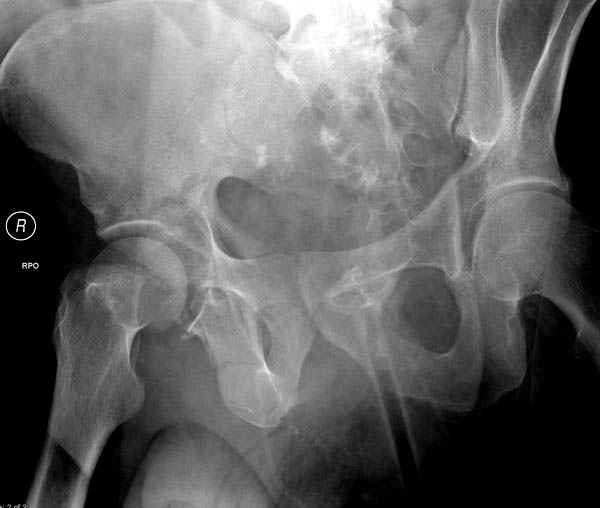

По снимку создается впечатление о высоком поперечном переломе, задней колонны, стенки; почему не пользовались *magic screw*?

Латеральное положение облегчает проведение тракции через вертел, за 5 мм стержень за вертел (грузом через тракционное приспособление), на обычном рентгенопрозрачном операционном столе, а для положения на животе, наверное, Judet Table более приемлем, потому что там имеется латеральное тракционное устроиство.

Там множество обычных 2.7 мм шурупов, потом идет фиксация основными пластинами.

Снимки здесь....